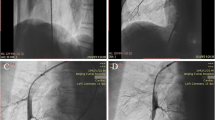

If a patient had multiple CMR studies, the most recent study with complete flow data was used for analysis. MPBF was calculated by direct measurement of the branch PA flow on phase contrast imaging. Branch PA flow was measured by manually tracing each branch PA on phase contrast imaging using QFlow (Medis Medical Imaging Systems, Leiden, The Netherlands) (Fig. 1a) [16]. Percentage flow to each PA was calculated. In patients without baffle leaks or patent fenestrations who had unilateral PA stents where direct PA flow could not be measured, flow in the stented PA was calculated using the following formula: superior vena cava flow+ inferior vena cava flow – the non-stented branch PA flow. Branch PA cross-sectional area was calculated by measuring two orthogonal dimensions at the narrowest segment and indexed to body surface area (Fig. 1b). A branch PA symmetry index (PASI) was calculated as the ratio of the area of the smaller pulmonary artery to the larger pulmonary artery. PASI is always ≤1 with values closer to 1 reflecting more symmetric branch PAs [17]. PA compression by the ascending aorta or aortic root was determined by review of CMR images by a provider who was blinded to the PA blood flow distribution. PA compression was defined as narrowing of the branch PA to < 75% of its original diameter as it crossed posterior to the ascending aorta or the aortic root (Fig. 1c) [18]. Lung volumes were calculated by Simpson’s method using manual tracing of the lung fields in each slice on an axial image bSSFP stack (Fig. 1d). Lung volume discrepancy was defined as the absolute value of the difference between the right and left lung volume percentage. Aortic root total area was measured by adding dominant to non-dominant aortic root area as measured on axial planes [19].

Cardiovascular magnetic resonance (CMR) example of different measurements used in our study. a Branch pulmonary artery (PA) flow measurement. b Branch PA cross-sectional area was calculated by measuring two orthogonal dimensions at the narrowest segment. c Left pulmonary artery (LPA) compression by a dilated ascending aorta. d Lung volume calculation by Simpson’s method using manual tracing in each slice on an axial image balanced steady-state free precession stack